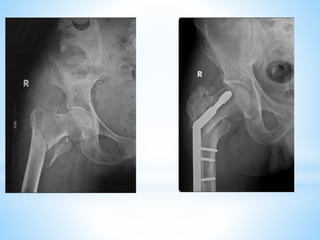

This document discusses the treatment of intertrochanteric hip fractures with different fixation devices. It notes that cephalomedullary devices are preferable to dynamic hip screws for fractures with posteromedial comminution or subtrochanteric extension due to their ability to provide controlled collapse and reduce bending forces. The document emphasizes the importance of pre-operative planning, proper reduction techniques, and achieving a tip-apex distance under 25mm for successful fixation with cephalomedullary devices.